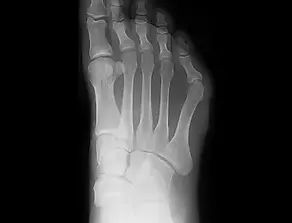

中足骨短縮症

足の中足骨が通常よりも短くなる状態を指します。成長期に中足骨の成長が早く止まることで生じますが、明確な原因はわかっていません。

怪我が関係している可能性がある一方、家族内で見られることも多く、遺伝的な要因が強いとも考えられています。特に第4趾に多く見られ、男性よりも女性に多い傾向にあります。この状態により、痛みが生じたり、足の指が変形しやすくなることがあり、見た目にも影響が出ることがあるため、治療を希望する方も少なくありません。